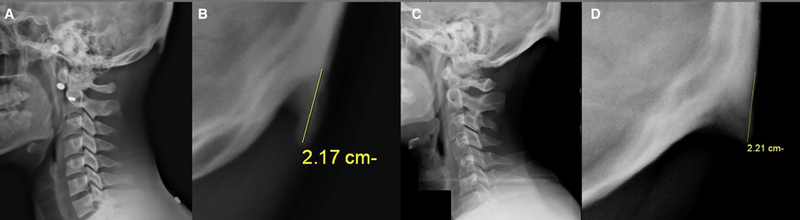

Avustralya’daki Sunshine Coast Üniversitesi’den bilim adamları Dr. David Shahar ve Prof. Mark Sayers, 18-30 yaş arasındaki 218 kişinin röntgen çekimlerini inceledi. Yapılan araştırmalar sonucu röntgen çekilen kişilerin neredeyse yarısının kafatası şeklinin yoğun cep telefonu ve tablet kullanımına bağlı olarak ‘değiştiği’, boynuzumsu bir çıkıntıya benzediği belirtildi.

Yapılan araştırmaya göre, gününün büyük kısmında teknolojik aletlere kafasını eğerek bakan gençlerin, kafatasındaki oksipital kemik denen bölge, görünür şekilde belirginleşmeye başlıyor.

Her 4 gençten birinde görülen bu durum, dijital ekranlar karşısında geçirilen süreyle ilgili endişelere bir yenisini daha ekliyor.